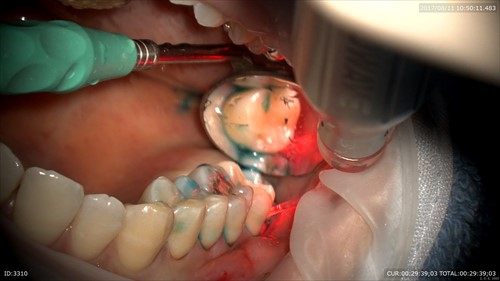

綺麗になりました。

そしてレーザー

一緒に画像をみながら笑って治療していました。歯ブラシを頑張っていただけるので歯周病がどんどん良くなりますね!充実した午前中でした。明日からのお盆休みに向け午後の診療もがんばりますーー。当院は18日までお休みを頂きます。